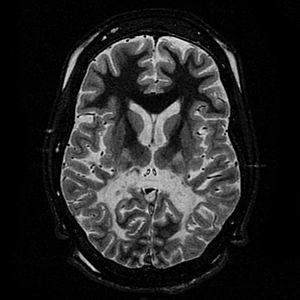

T2 weighted axial scan at the level of the caudate heads demonstrates marked loss of posterior white matter, with reduced volume and increased signal intensity. The anterior white matter is spared. Features are consistent with X-linked adrenoleukodystrophy.

The degeneration of white matter, which shows the degeneration of myelin, can be seen in a basic MRI and used to diagnose leukodystrophies of all types. T-1 and T-2 weighted FLAIR images are the most useful. FLAIR stands for fluid-attenuated inversion recovery.[25] Electrophysiological and other kinds of laboratory testing can also be done. In particular, nerve conduction velocity is looked at to distinguish between leukodystrophy and other demyelinating diseases, as well as to distinguish between individual leukodystrophies. For example, individuals with X-ALD have normal conduction velocities, while those with Krabbe disease or metachromatic leukodystrophy have abnormalities in their conduction velocities.[25] Next generation multigene sequencing panels for undifferentiated leukodystrophy can now be offered for rapid molecular diagnosis after appropriate genetic counselling.